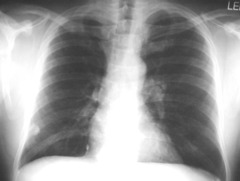

Why is the prognosis for lung cancer usually so poor?

Often no symptoms before metastasis

Leading cause of death by cancer

Lung

Three leading causes of death by cancer

Lung; Breast/Ovarian, Prostate; Colorectal